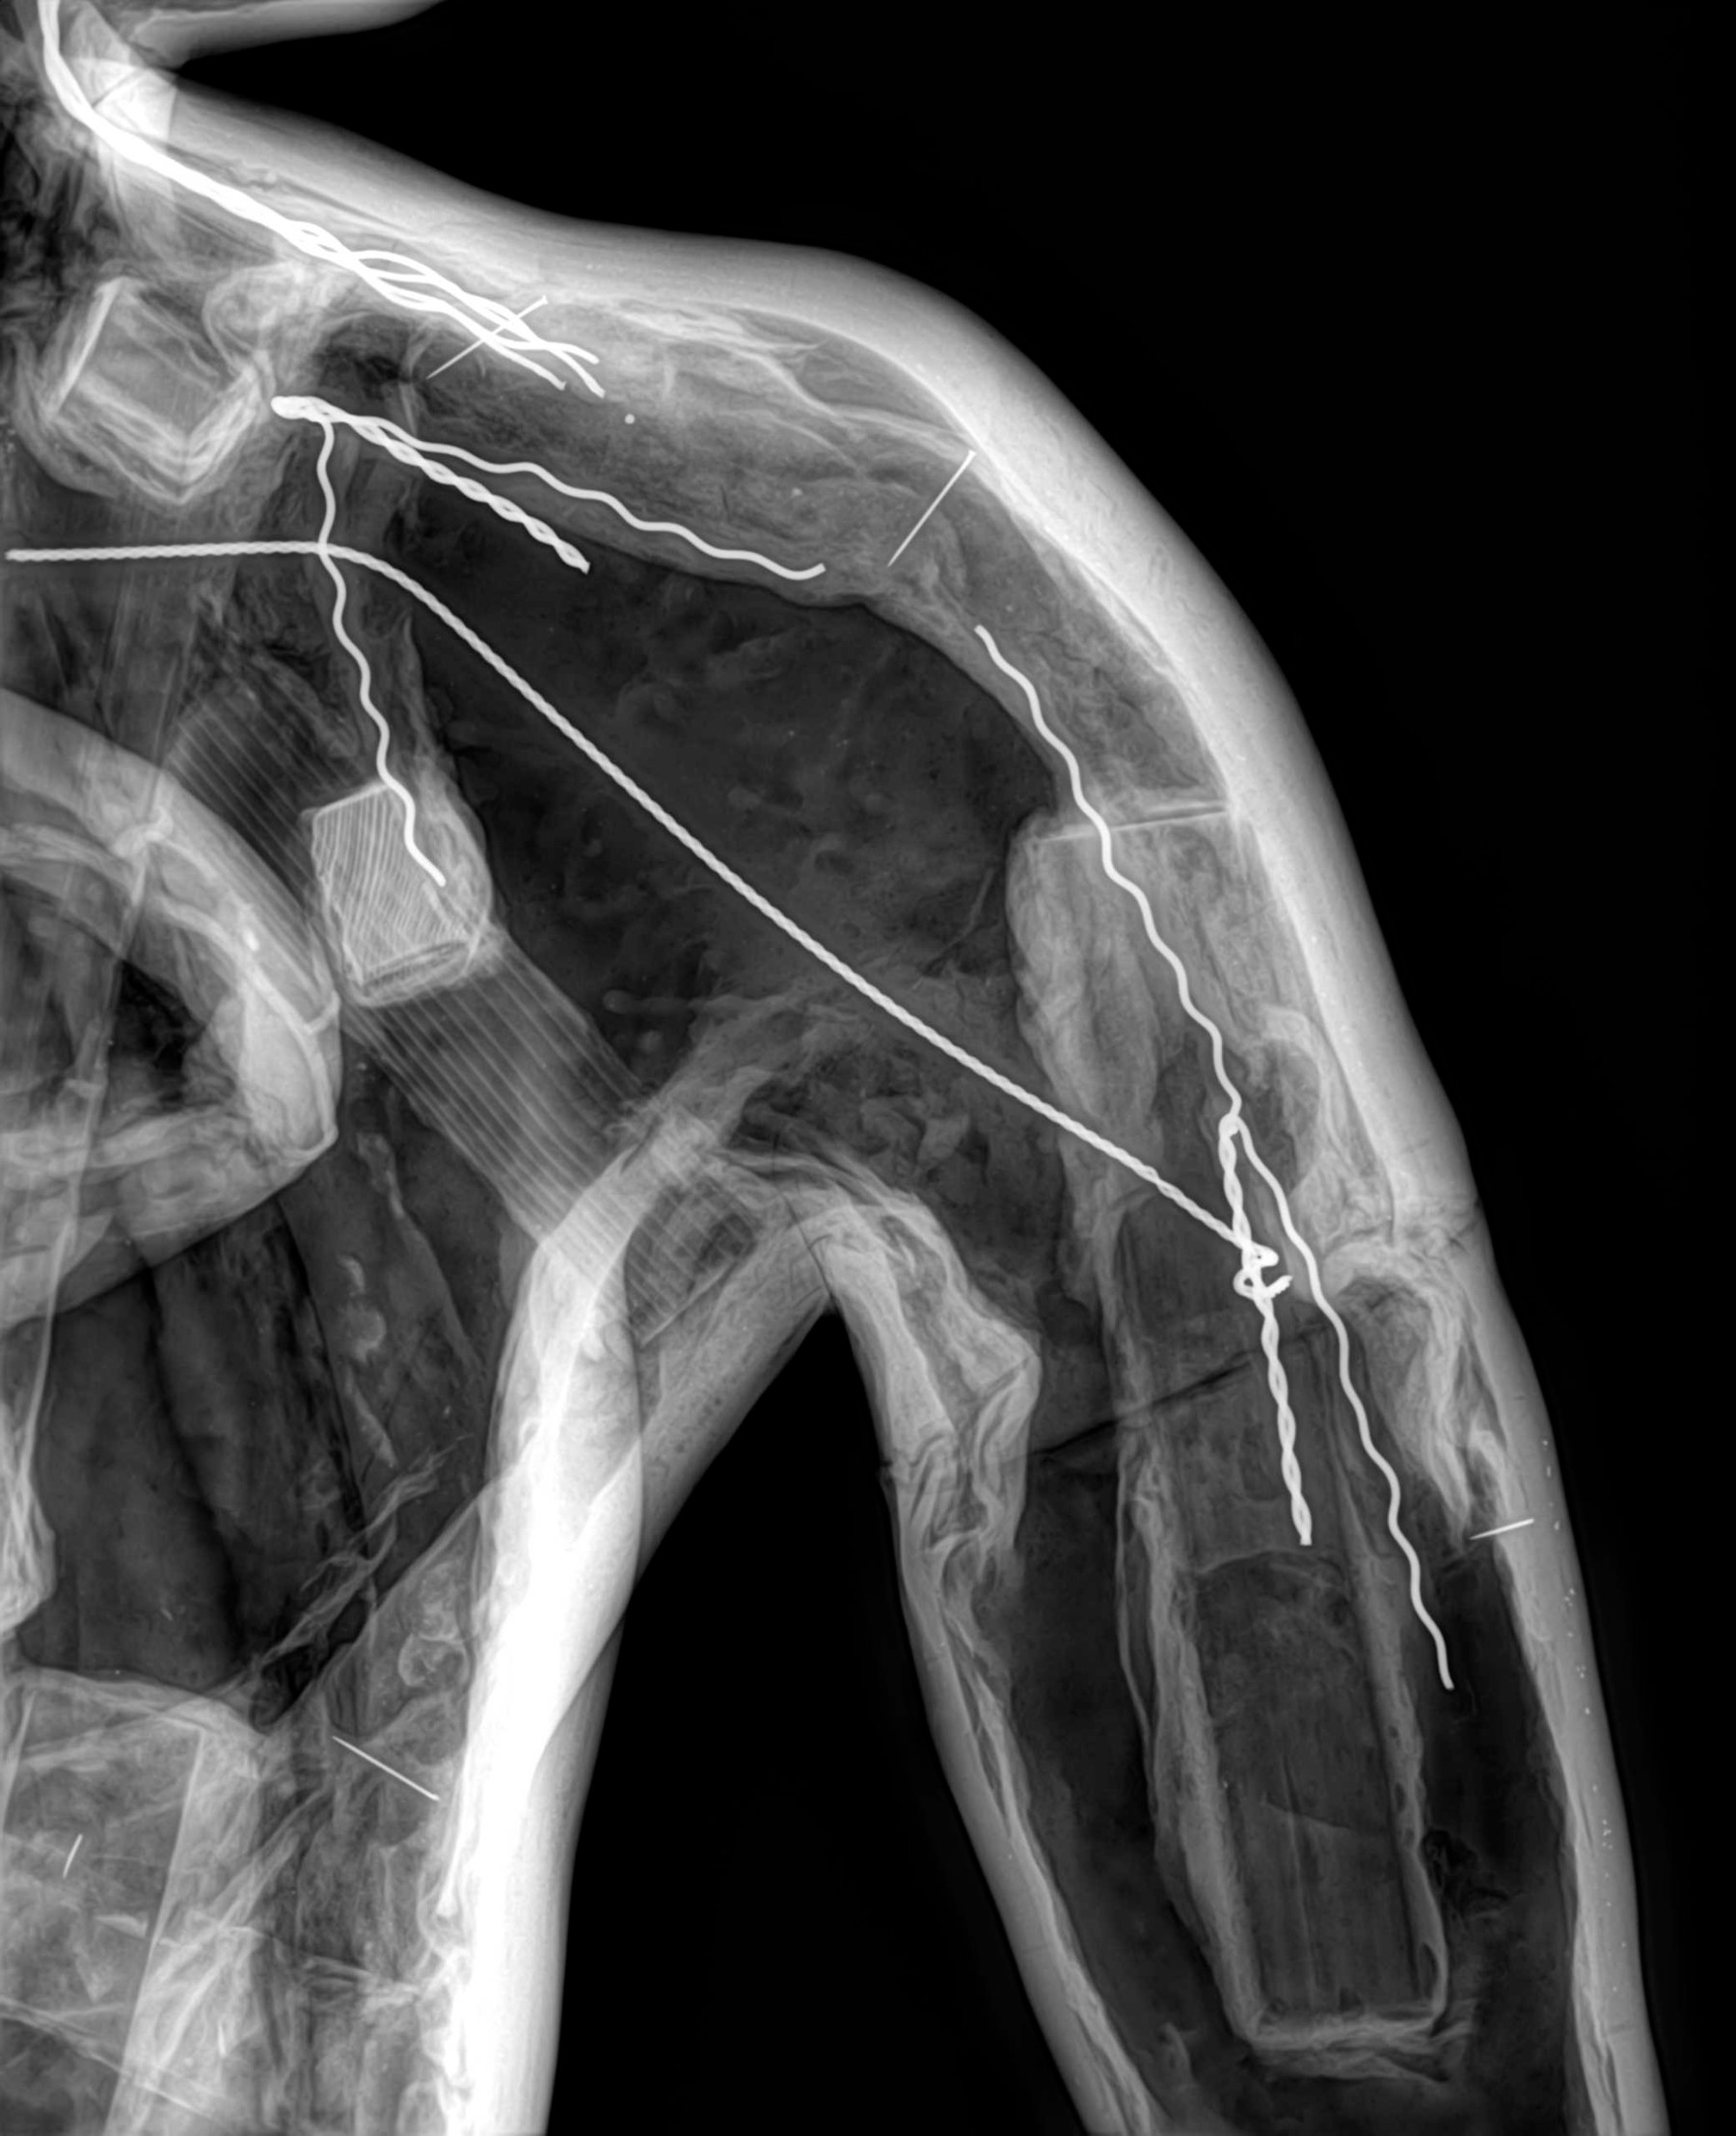

Radiología Digital como Herramienta Complementaria en el Dictamen de Bienes Muebles